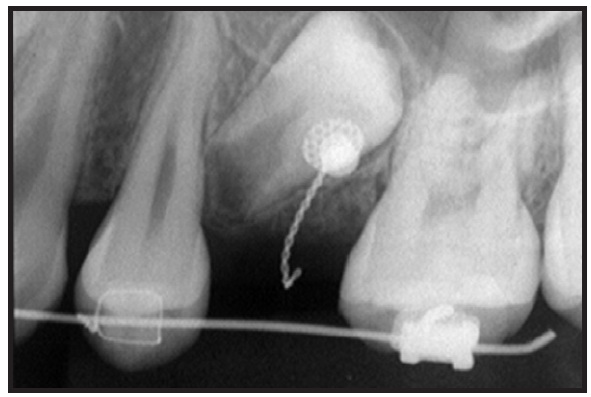

After seven days of healing, orthodontic treatment was resumed. Traction was applied to the twisted stainless steel ligature to bring about full eruption of the tooth. Since the distance between the ligature wire and the main archwire was too short to apply force, a stepdown bend was made in the archwire, and an open-coil spring was inserted between the first molar and first premolar to open and maintain adequate space for the second premolar (Fig. 3). The progress of impacted tooth movement was evaluated monthly (Fig. 4). After three months, to produce more clockwise rotation of the impacted tooth, the metal button was replaced by a minitube and an .016" × .022" TMA*** auxiliary wire was bent and attached (Fig. 5). Three months later, the wire was activated to create an additional rotational moment (Fig. 6).

In another four months, the crown had been sufficiently rotated to replace the minitube with a bracket, and a segmental .014" nickel titanium wire was inserted for alignment (Fig. 7). The inverted upper left second premolar was successfully positioned in proper alignment within another 10 months (Fig. 8). After a total 23 months of treatment, the fixed appliances were removed and an upper 2-2 lingual retainer wire was bonded. Follow-up records taken three years after treatment confirmed the stability of results (Fig. 9).